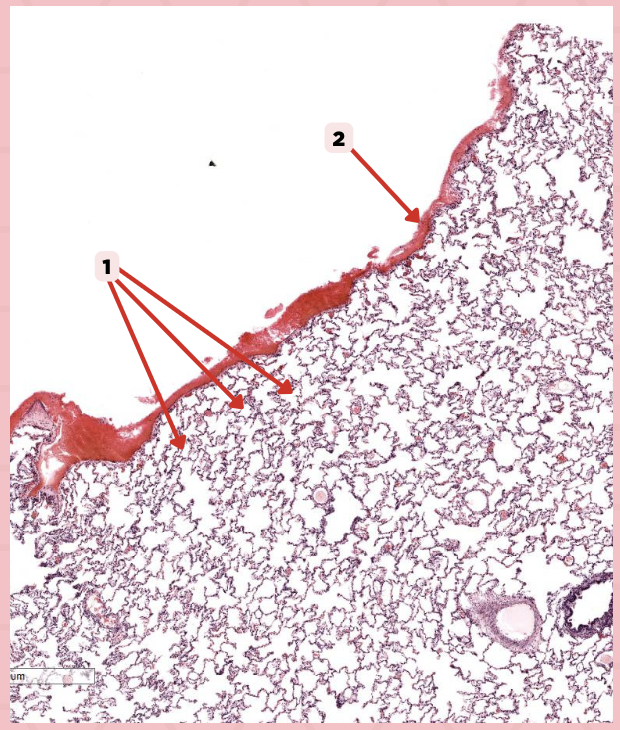

Simple squamous epithelium (Mesothelium)

The surface related to the pleural cavity is in line with what type of epithelium?

Lumens and Interalveolar septa

Name the irregular spaces and the fine threads of tissue that separate them.

Visceral pleura

Identify the structure labeled as 1.

Alveoli

Visceral Pleura

What type of pleura is a thin layer of connective tissues that borders on the outside by mesothelium?

Simple Squamous Epithelium

What epithelium lines the red arrow?

Mesothelium

Identify the structure labeled as 1.

Pulmonary Capillaries

Oxygenated blood is collected by structure #2 from what source/structure?